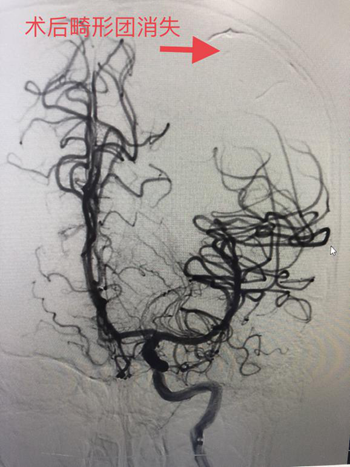

(术前造影图)                     (术后造影图)

近日,廖驭国团队成功抢救一名动静脉畸形破裂出血的14岁儿童。该患者经外院紧急转送至我院,入院时神志嗜睡,外院CT提示左侧颞顶叶急性脑出血。神经外科首诊医生廖军研判,患者高度疑似颅内动静脉畸形破裂出血,“时间就是大脑”情况十分紧急,急需手术治疗,马上汇报神经外科主任、神经介入中心主任廖驭国同时向家属解释病情并经得同意后,在麻醉科医生精准麻醉和严密检测下,廖驭国带领神经外科李海堃副主任医师为患者进行颅内动静脉畸形栓塞术,术中完美栓塞畸形团,顺利完成手术。